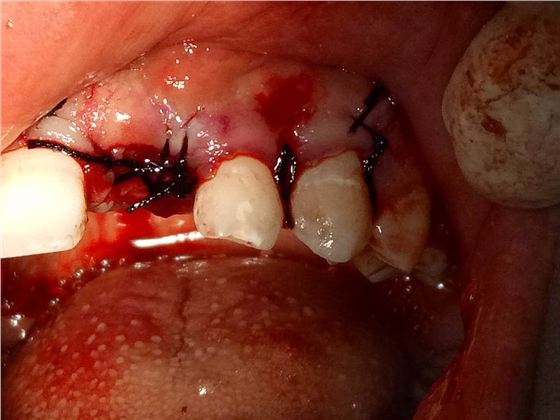

死髓牙2度,沒(méi)保留價(jià)值了,外傷造成的外吸收,即使到充也容易出問(wèn)題。和患者溝通,要求做種植,用了兩個(gè)骨膠原,側(cè)切、尖牙沒(méi)事,側(cè)切做了一次根充